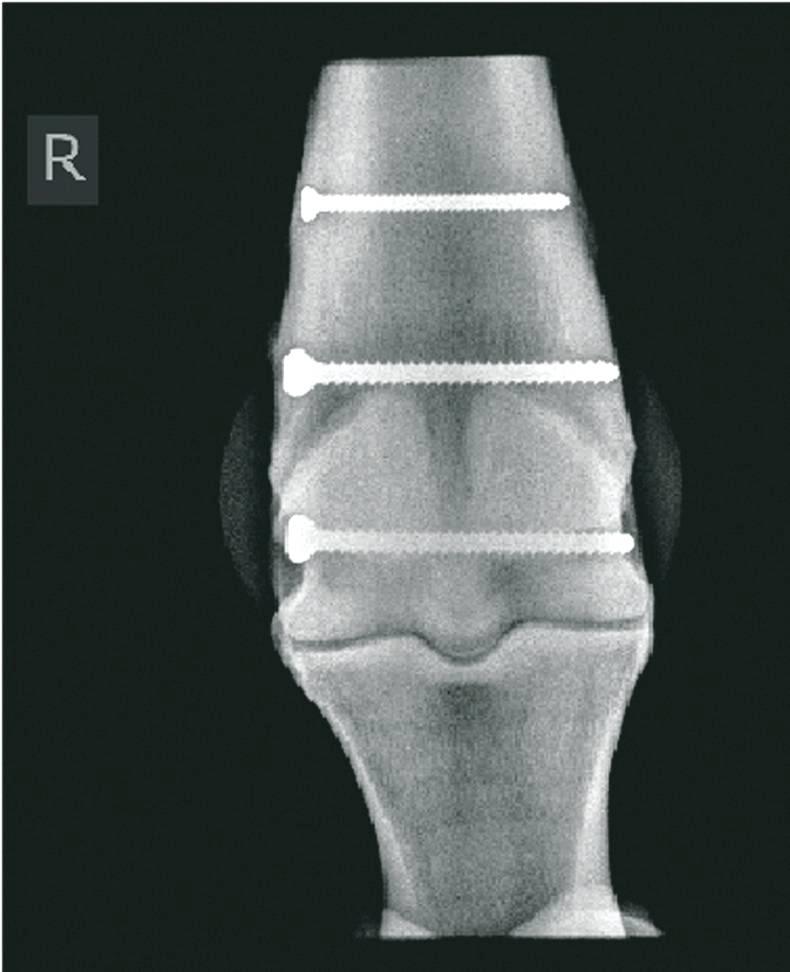

CONDYLAR fractures refer to fractures of the lower part of the cannon bone. The medial and lateral condyles are rounded prominences of the lower cannon bone which articulate with the long pastern bone forming the fetlock joint.

They are the most common fracture seen in the long bones of racehorses. Condylar fractures are twice as likely to occur in forelimbs and four times more likely to occur in the lateral condyle compared with the medial condyle.